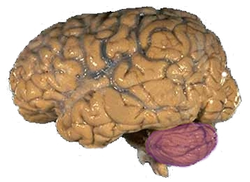

الشكل 1a: مخ بشري، ويظهر فيه المخيخ باللون البنفسجي

المخيخ Cerebellum هو القسم الكروي الأصغر الذي يقع أسفل نصفي الكرة المخيتين في الدماغ ، يهتم المخيخ بشكل أساسي بوظائف التوازن و تنظيم الوظائف الحركية. يقع أسفل النصفين الكرويين في الجهة الخلفية للمخ ويتركب من فصين أيمن وأيسر يصل بينهما فص ثالث.